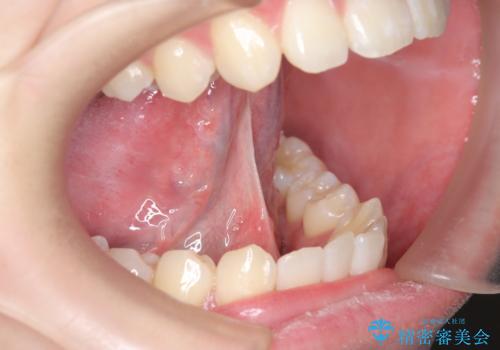

成人の舌小帯切除 舌が動かしにくい